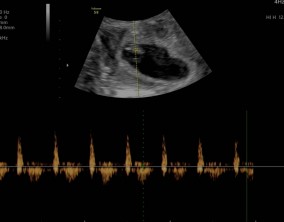

임신 수치 16, 9주차 기적의 기록

서울IVF에서는 단순히 배아 생성과 이식만 해주시는 것이 아니라, 제 생활 전반까지 신경 써주셨습니다. 휴식기에도 그저 기다리는 것이 아니라 항노화에 도움이 되는 링겔을 처방…